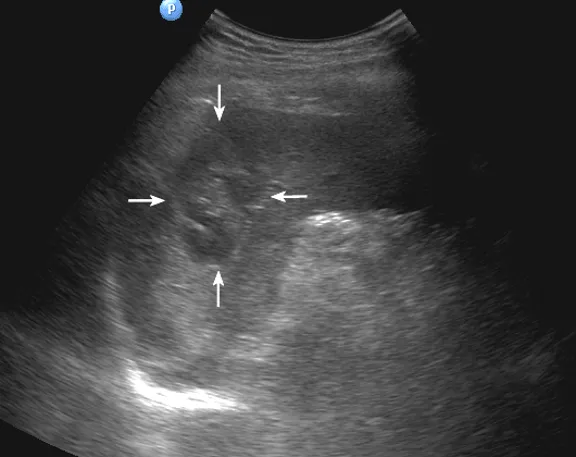

灰阶超声显示脾内多个低回声团块,呈分叶状,形态不规则(箭头所示)。